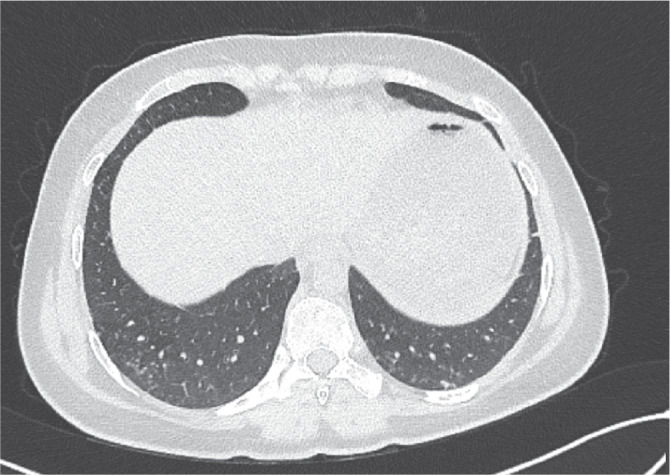

Everolimus is one of the immunosuppressive drugs used in solid organ transplantation. Many side effects have been described for these immunosuppressive drugs, similar to other drugs in this category. The purpose of this case presentation is to draw attention to drug-induced pneumonitis, which is a rare and life-threatening side effect of everolimus. A nineteen-year-old female patient who received liver transplantation for toxic hepatitis was admitted to our institute with cough and dyspnea. Everolimus had been started in conjunction with tacrolimus therapy 6 months prior to admission. Her chest imaging were consistent with pneumonitis. Markers of infection and cultures were all negative. After discontinuation of everolimus, symptoms and radiological findings resolved. The adverse effects of the drug should be kept in mind while investigating possible infectious agents in liver transplant recipients who are prone to opportunistic infections.

Abstract Image